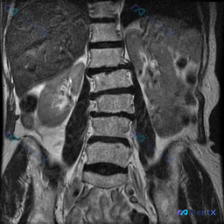

整理到一份腹部MRI的影像分析资料,有点意思——用户最初的疑问是“这张图能看到脊柱侧弯吗”,但读下来发现,真正可能需要紧急处理的问题不在脊柱,而在脾脏。 先不说结论,先放关键影像表现: 1. 肝脏、胆道、胰腺、双肾(除右肾位置稍低)未见明显重大异常; 2. 脾脏明显增大,下极到腰椎中下段,实质内弥漫...

整理到一份影像资料,有点意思。 用户一开始先提了“脊柱侧弯(Scoliosis)”,这是腹部MRI的T2加权冠状位。 先不说预设,光看影像里的客观描述: - 腰椎各椎体序列连续,骨质信号、椎间盘都没说有大问题 - 双肾大小形态还行,但左肾(图右侧)中下部有个类圆形的T2高信号,边界清,信号均匀,跟尿...